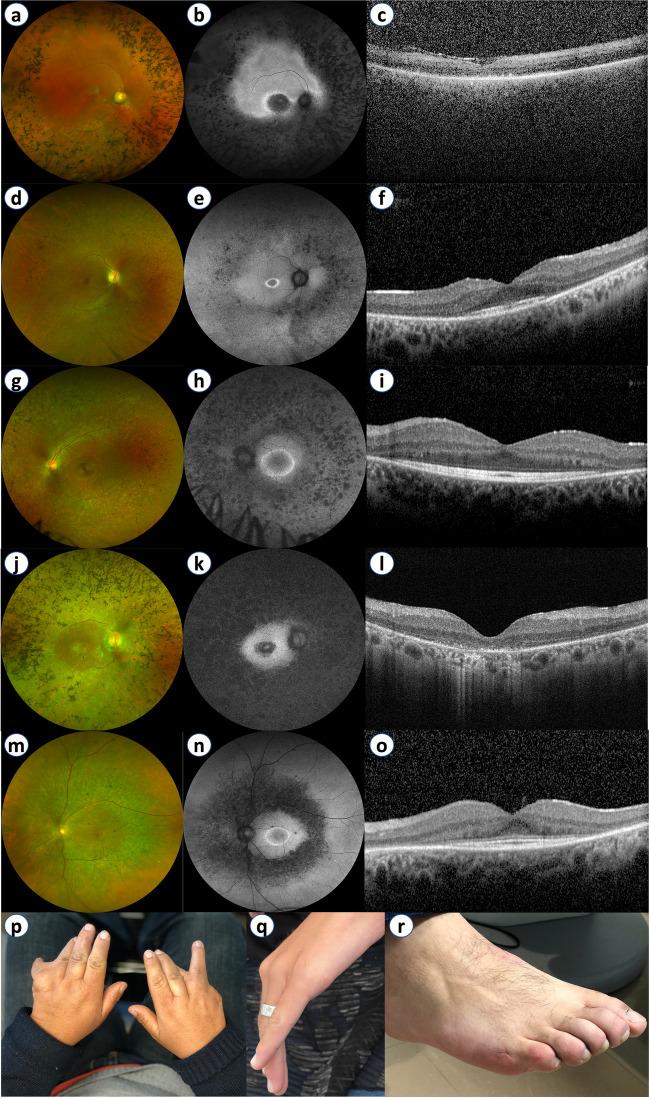

葡萄牙综合征性视网膜炎的遗传特征。

Genetic profile of syndromic retinitis pigmentosa in Portugal.

Retinitis pigmentosa (RP) comprises a genetically and clinically heterogeneous group of inherited retinal degenerations, where 20-30% of patients exhibit extra-ocular manifestations (syndromic RP). Understanding the genetic profile of RP has important implications for disease prognosis and genetic counseling. This study aimed to characterize the genetic profile of syndromic RP in Portugal.

RESULTS

One hundred and twenty-two patients (53.3% males) from 100 families were included. Usher syndrome was the most frequent diagnosis (62.0%), followed by Bardet-Biedl (19.0%) and Senior-Løken syndromes (7.0%). Deleterious variants were identified in 86/100 families for a diagnostic yield of 86.0% (87.1% for Usher and 94.7% for Bardet-Biedl). A total of 81 genetic variants were identified in 25 different genes, 22 of which are novel. USH2A and MYO7A were responsible for most type II and type I Usher syndrome cases, respectively. BBS1 variants were the cause of Bardet-Biedl syndrome in 52.6% of families. Best-corrected visual acuity (BCVA) records were available at baseline and last visit for 99 patients (198 eyes), with a median follow-up of 62.0 months. The mean BCVA was 56.5 ETDRS letters at baseline (Snellen equivalent ~ 20/80), declining to 44.9 ETDRS letters (Snellen equivalent ~ 20/125) at the last available follow-up (p < 0.001).